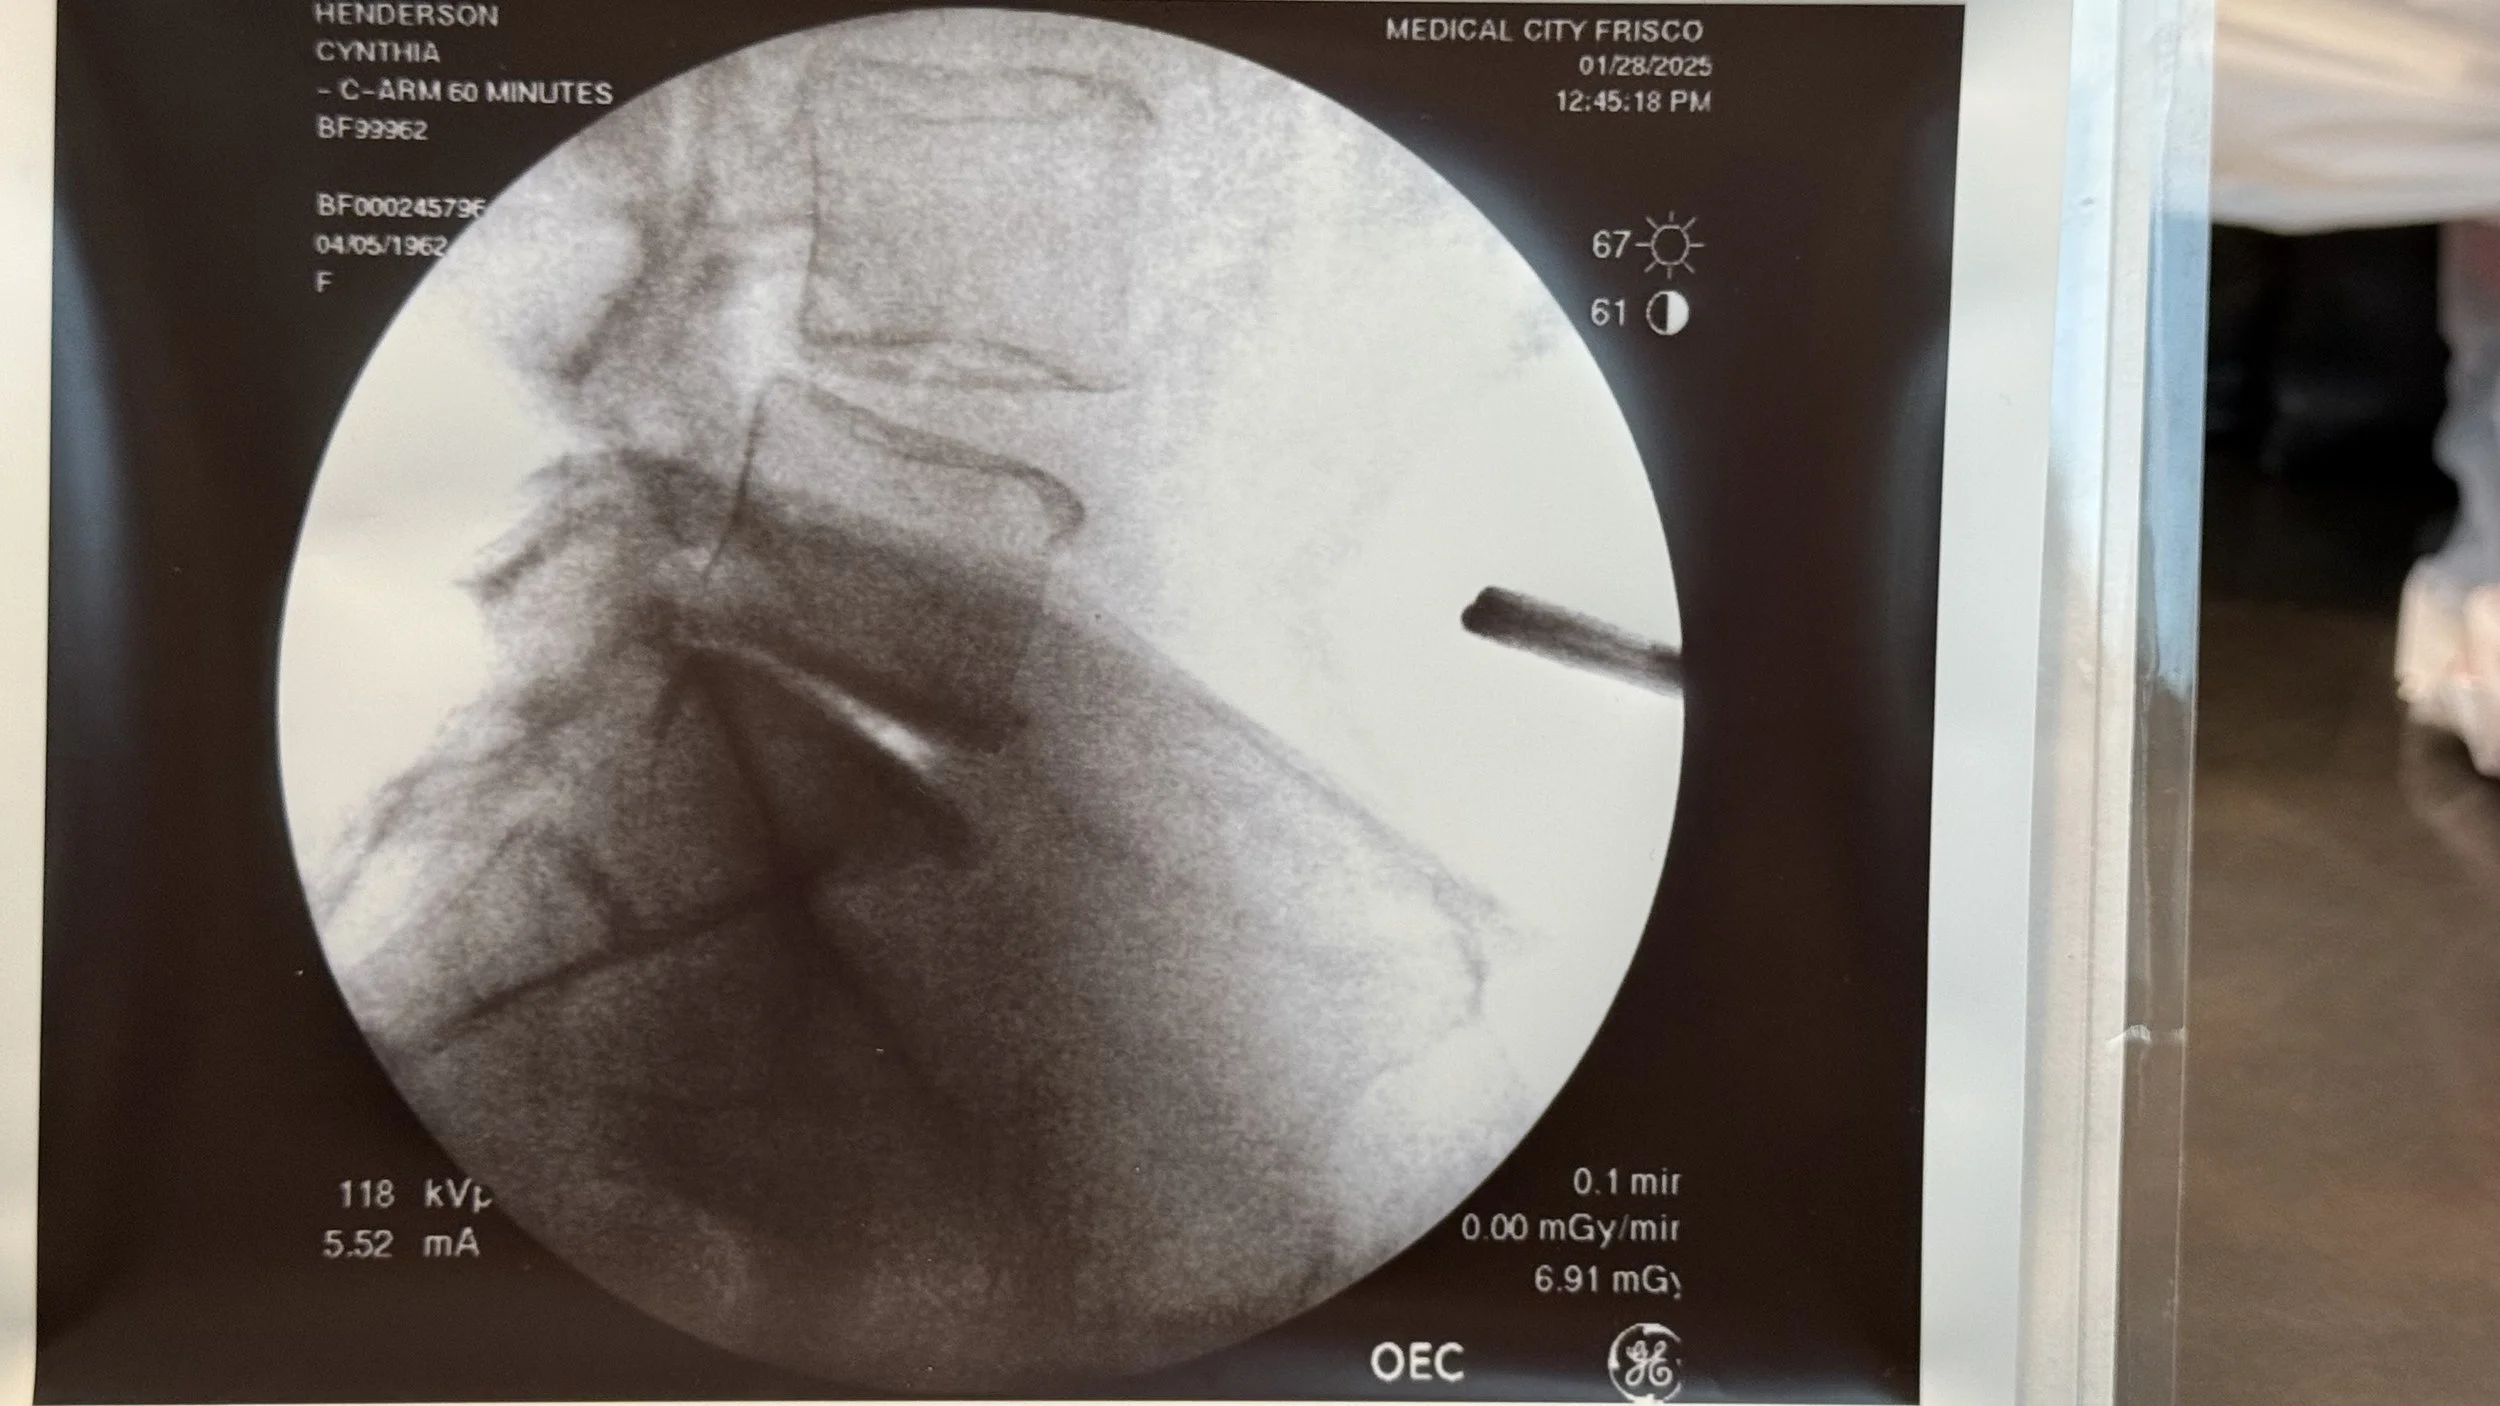

Before. Notice the gap near the bottom. There is a bright spot and bone on bone. Compare to the gap below.

Previous